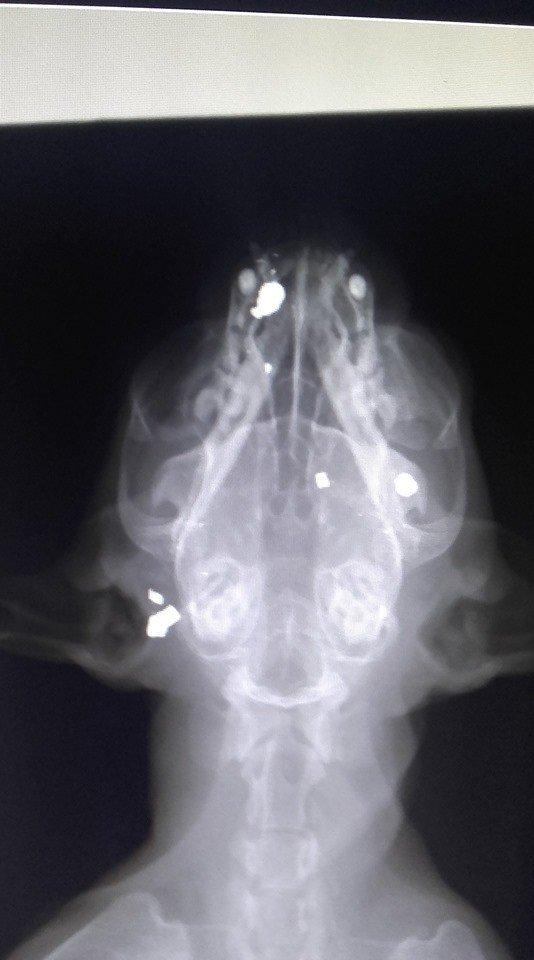

Όπως καταγγέλει ο Φιλοζωικός σύλλογος Χανίων, ένας γάτος βρέθηκε το πρωί της Τρίτης, στην οδό Παλαμά, στην μέση του δρόμου σε κατάσταση σοκ. Είναι το δεύτερο περιστατικό που σημειώνεται μέσα σε σύντομο χρονικό διάστημα. Μέλος του συλλόγου τον μετέφερε στο κτηνιατρείο και από τις ακτινογραφίες διαπιστώθηκε ότι είναι πυροβολημένος σε όλο το κεφάλι, με αποτέλεσμα να έχει χάσει την όρασή του και σχεδόν την ακοή του .

Επιπλέον, ποαρουσιάζει αστάθεια στη βάδιση, αλλά ακόμα δεν είναι γνωστό αν είναι παροδική ενώ αξίζει να σημειωθεί ότι δεν έχει πλήρη αντίληψη του χώρου.